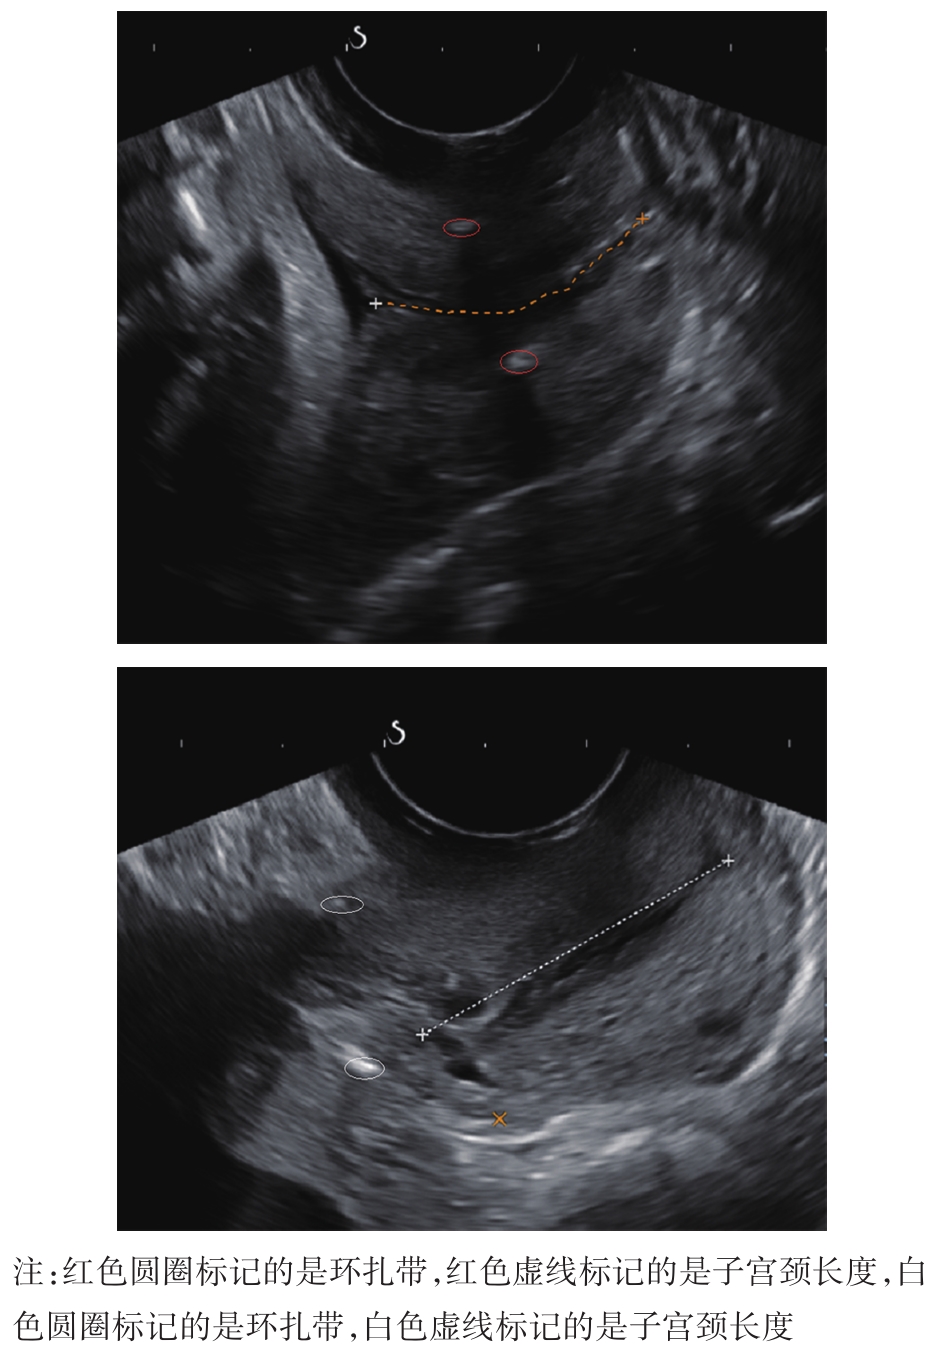

• 宫颈机能不全患者孕期腹腔镜和经阴道宫颈环扎术后的疗效分析

摘要:目的 探讨子宫颈机能不全(cervical incompetence,CI)患者孕期行腹腔镜子宫颈环扎术(laparoscopic cervical cerclage,LAC)和经阴道子宫颈环扎术(transvaginal cervical cerclage,TVC)后的妊娠结局及超声监测妊娠期子宫颈长度的变化,进一步探讨LAC的适应证。方法 回顾性分析2016年6月至2022年2月因CI孕期在本院行子宫颈环扎术的患者共115例,其中行LAC 65例(LAC组),既往TVC失败35例,既往行子宫颈锥切术30例;TVC 50例(TVC组),均无既往TVC失败史,既往行子宫颈锥切术20例。对2组患者的妊娠结局、术中情况、术后并发症及妊娠期超声测量的子宫颈长度进行比较。结果 LAC组既往TVC失败率高于TVC组(53.8% vs. 0.0%,P<0.05),差异有统计学意义,LAC组、TVC组既往子宫颈锥切手术率差异无统计学意义(46.1% vs. 40.0%,P>0.05);LAC组的足月产率、新生儿存活率、分娩孕周、延长孕周[83.0%、100.0%、(36.5±4.0)周、(17.0±4.2)周]均明显高于TVC组[44.0%、76.2%、(32.0±5.2)周、(13.2±4.3)周],差异有统计学意义(P<0.05);TVC组的早产率、难免流产率(40.0%、16.0%)均明显高于LAC组(12.3%、4.6%),差异有统计学意义(P<0.05);LAC组无术后并发症,TVC组术后发生并发症8例(16.0%),其中子宫颈裂伤1例,术后感染7例,TVC组术后并发症发生率较LAC组高(P<0.05)。2组术前子宫颈长度相似。行子宫颈环扎术后,2组环扎带与子宫颈外口之间的距离比较,差异有统计学意义[LAC组:(28.7±4.6)mm vs. (12.3±4.2) mm,P<0.05],妊娠期间,TVC组子宫颈长度明显缩短[分娩时,由术前的(25.0±2.0) mm缩短为(12.0±4.5) mm,P<0.05],而LAC组子宫颈长度保持不变。结论 CI患者孕期行LAC安全、有效,妊娠结局较TVC好,原因可能是与TVC相比,LAC能更好地保留妊娠期间的子宫颈长度,推荐对既往TVC失败及既往子宫颈锥切术后子宫颈过短的患者首选LAC。